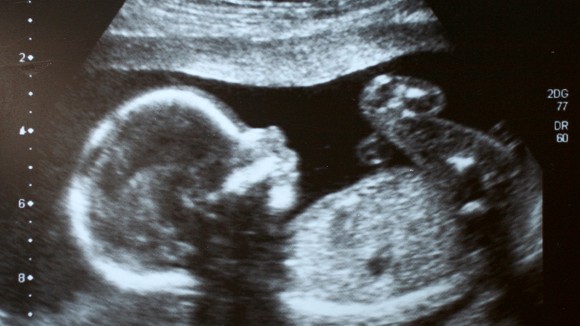

Terobosan: Bayi Pertama di Dunia Disembuhkan dari Penyakit Saraf Saat Masih Dalam Kandungan

Seorang gadis berusia dua setengah tahun tidak menunjukkan tanda-tanda penyakit genetik langka setelah menjadi orang pertama yang diobati untuk kondisi motor neuron saat masih dalam kandungan. Ibunya mengonsumsi obat yang menargetkan gen selama kehamilan, dan anak tersebut terus mengonsumsinya. Dokter mengatakan bahwa anak tersebut telah diobati secara efektif dan tidak menunjukkan gejala penyakit yang dikenal sebagai atrofi otot spinal (SMA), yang dapat menyebabkan kelemahan otot progresif dan biasanya berakibat fatal pada anak-anak.

Penyakit ini disebabkan oleh kurangnya gen SMN1 yang penting untuk menjaga neuron motorik. Dalam penelitian ini, obat yang digunakan adalah Risdiplam, yang membantu meningkatkan produksi protein yang diperlukan. Sebelumnya, pengobatan untuk SMA diberikan setelah lahir, tetapi penelitian ini menunjukkan bahwa memberikan obat sebelum lahir bisa menjadi langkah yang lebih baik untuk mencegah gejala penyakit.